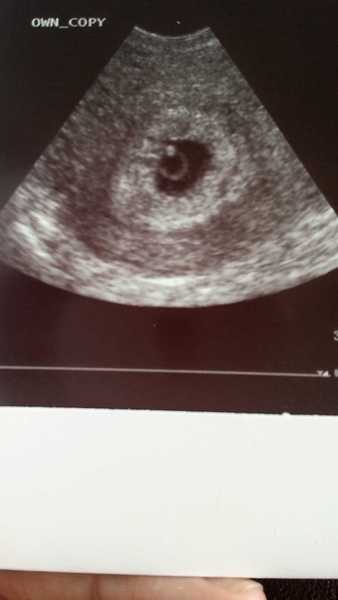

Hi all. Mind if I hop on? Due no.1 around the 11th February. Already had an early scan due to pcos. I had my booking in appt today midwife was lovely and i've got my 12 week scan on the 21st! Here is a pic of my blob it looks like I have swallowed a diamond ring!!